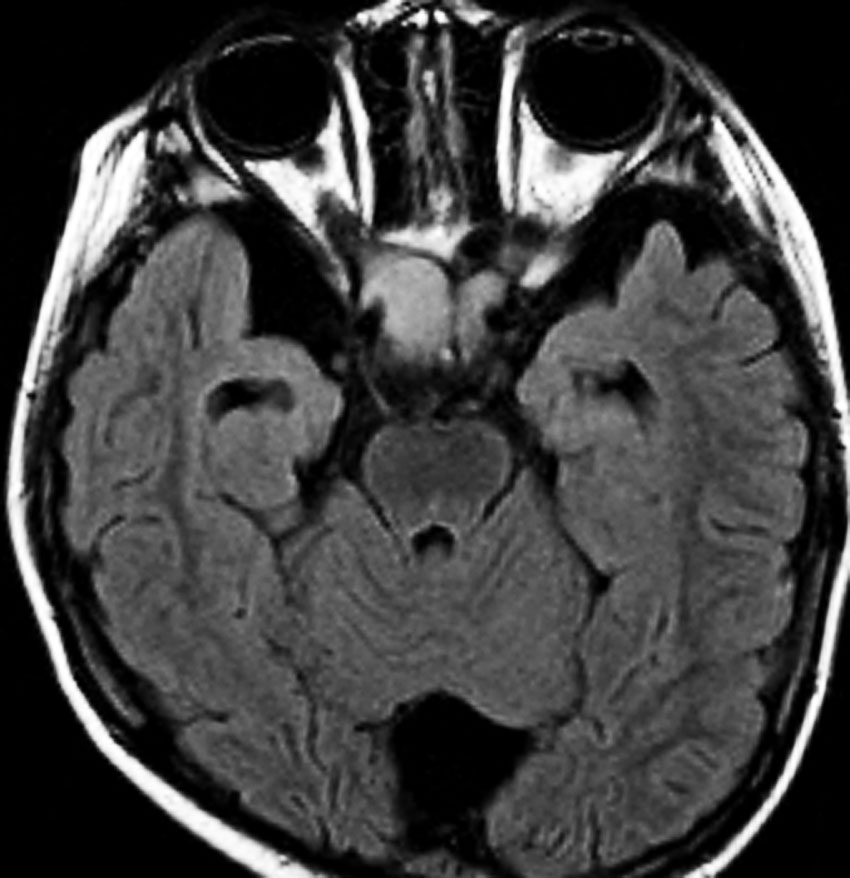

whole optic pathway pilocytic astrocytomaとは

両側の眼窩内視神経から視交叉、視索,外側膝状体,内包後脚,視放線近位部までが腫瘍化しています。FLAIRで高信号で,不規則にガドリニウム増強されます。これを手術摘出したり生検したりしても無駄です。放射線治療は不可能であり治療方法は化学療法のみです。

この子はCDDP/VCRの化学療法から開始して12年になりますが,今は無治療でわずかな視力ですが学校に通っています。優等生です。自然退縮を見ていますが,今後も変化する可能性はすこし残しています。